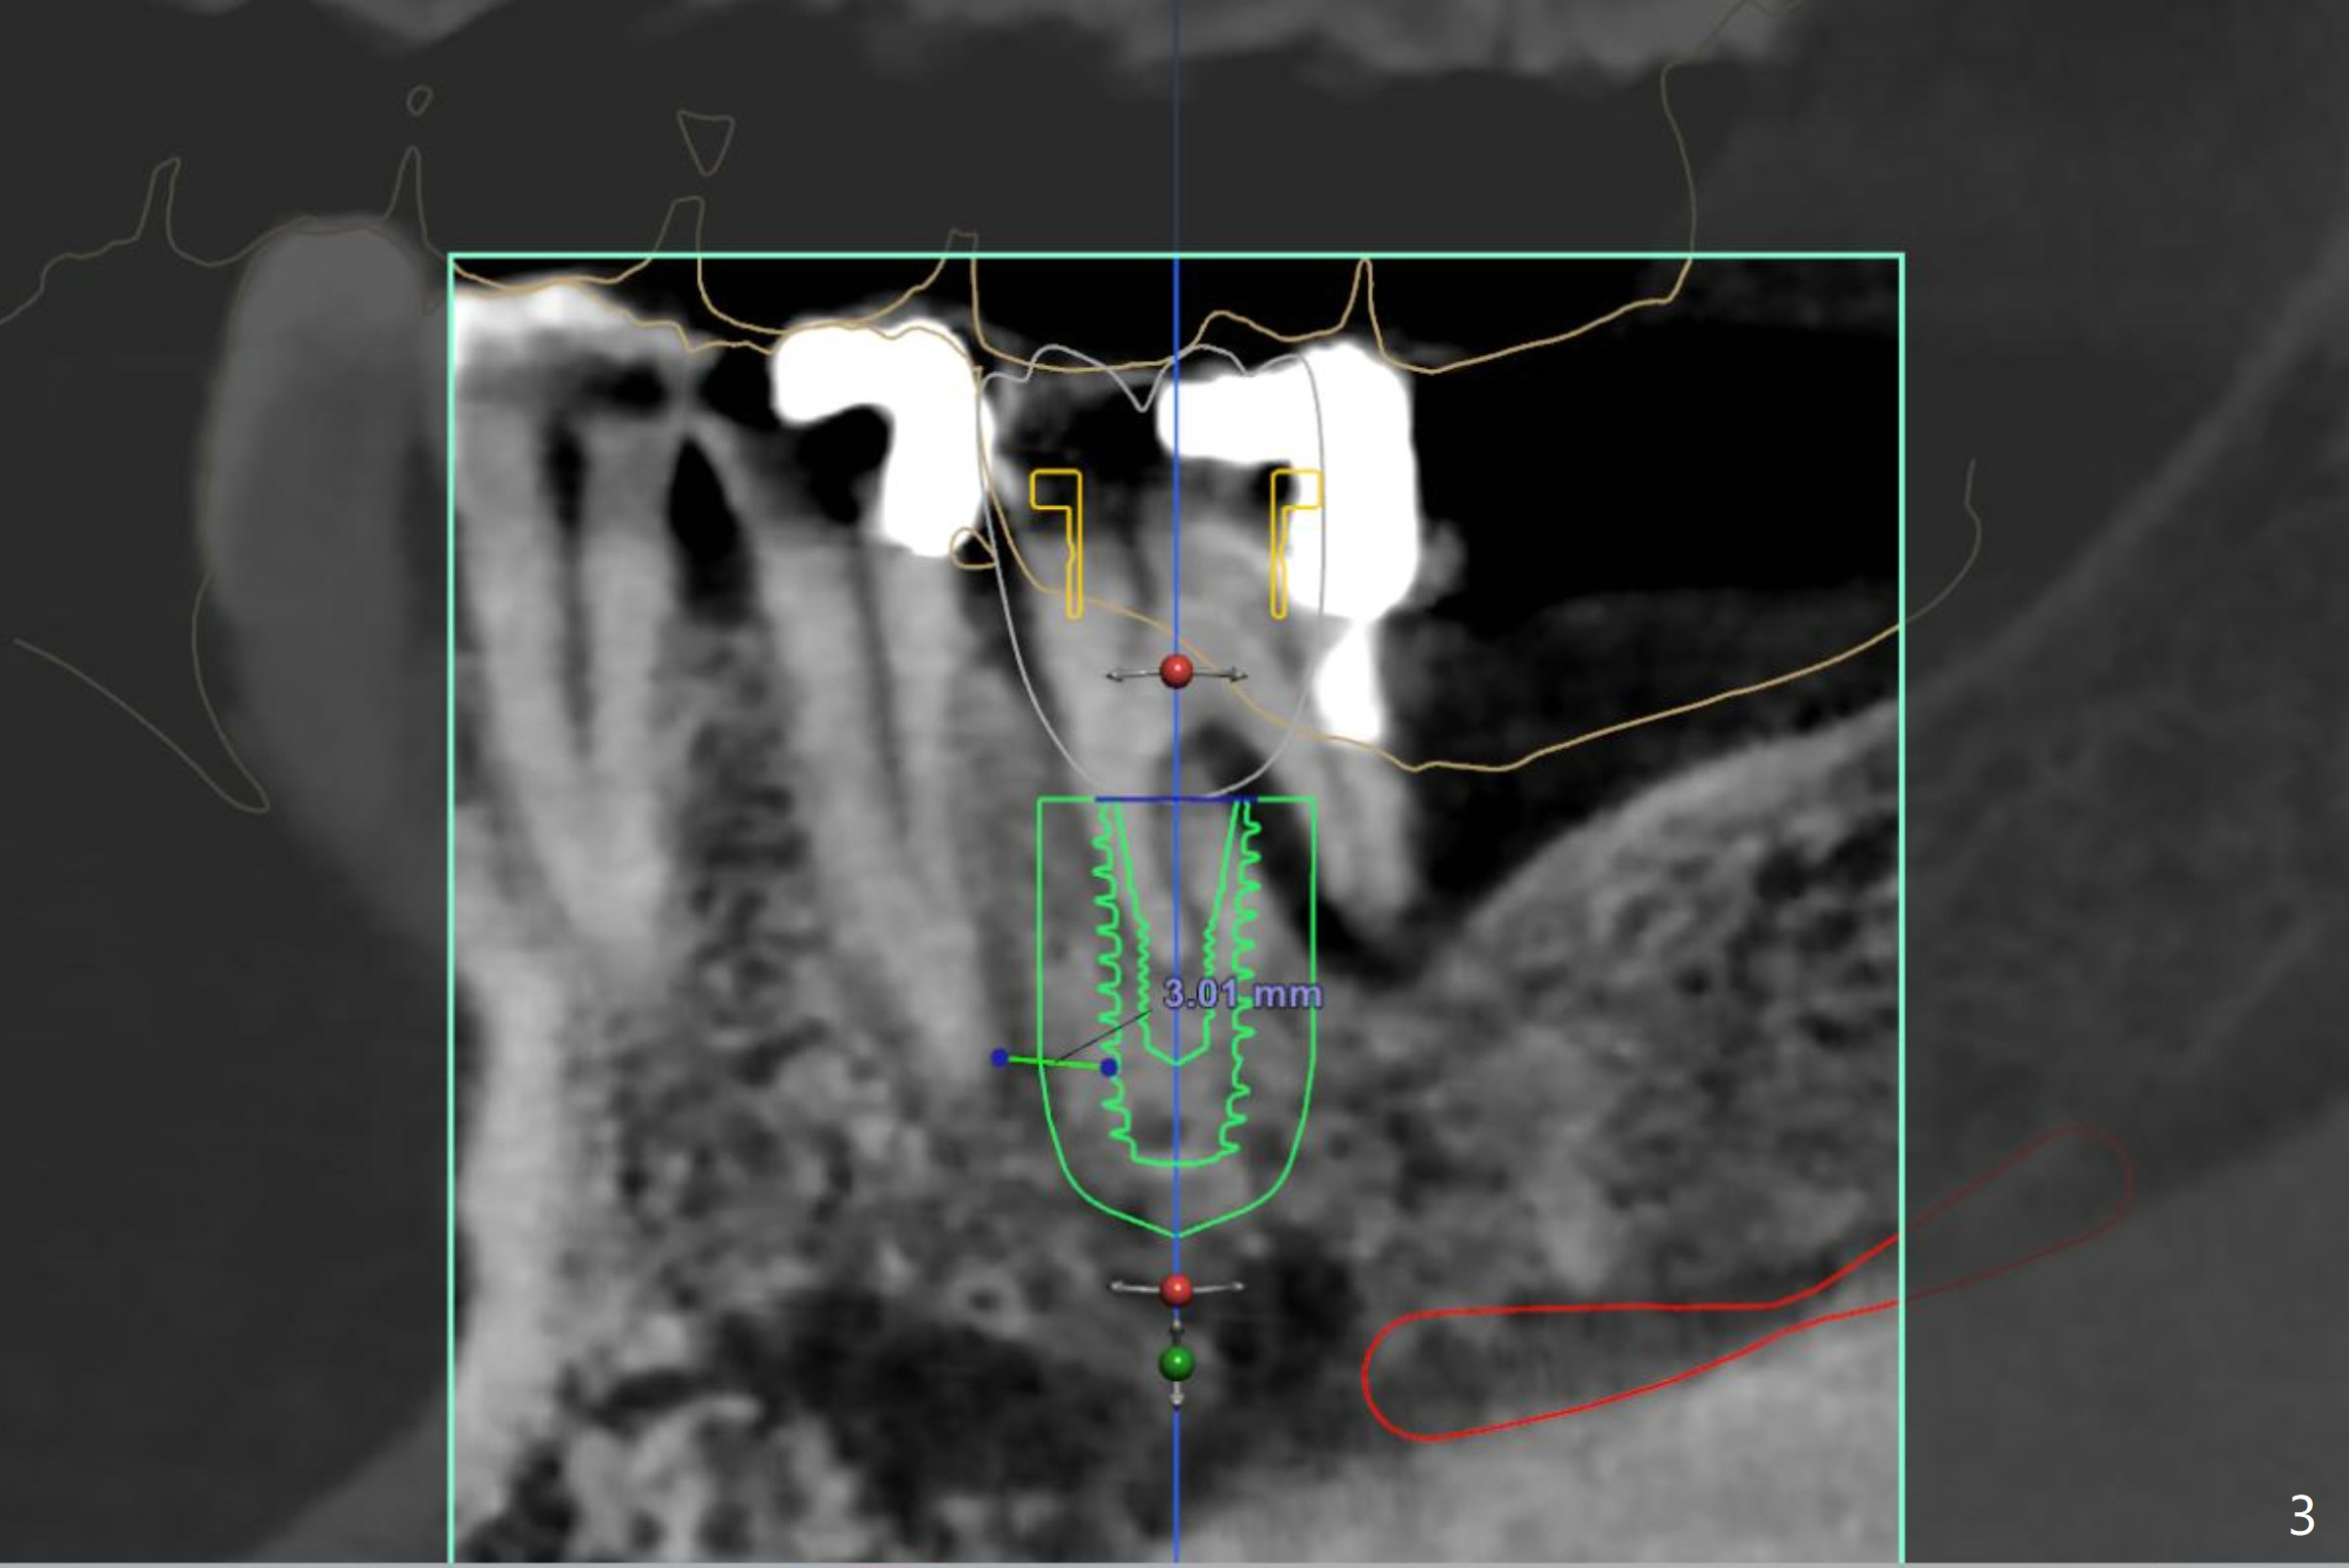

Lower Molar Immediate Implant, Trajectory Xin Wei, DDS, PhD, MS 1st edition 12/06/2018, last revision 12/13/2018